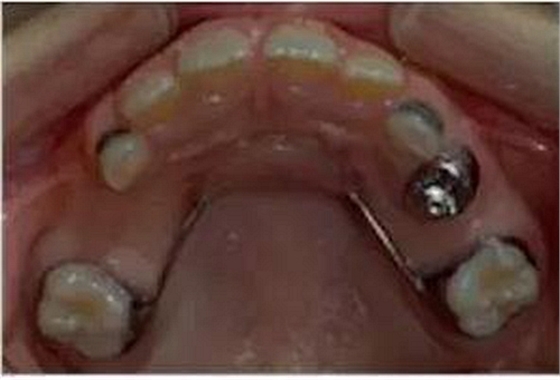

③Nance弓(腭弓)式間隙保持器

乳牙缺失致恒牙“亂長”,這個“間隙保持器”可預防

Nance弓式間隙保持器,也稱為腭弓式間隙保持器,是用于上牙需要間隙保持的部位,它和舌弓式間隙保持器是相對應(yīng)的。